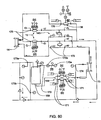

- Fig. 1 is a schematic representation of a hemodialysis system.

- the system 5 includes two flow paths, a blood flow path 10 and a dialysate flow path 20.

- Blood is drawn from a patient.

- a blood flow pump 13 causes the blood to flow around blood flow path 10, drawing the blood from the patient, causing the blood to pass through the dialyzer 14, and returning the blood to the patient.

- the blood may pass through other components, such as a filter and/or an air trap 19, before returning to the patient.

- anticoagulant may be supplied from an anticoagulant supply 11 via an anticoagulant valve 12.

- a dialysate pump 15 draws dialysate from a dialysate supply 16 and causes the dialysate to pass through the dialyzer 14, after which the dialysate can pass through a waste valve 18 and/or return to the dialysate feed via dialysate pump 15.

- a dialysate valve 17 controls the flow of dialysate from the dialysate supply 16.

- the dialyzer is a type of filter having a semi-permeable membrane, and is constructed such that the blood from the blood flow circuit flows through tiny tubes and the dialysate solution circulates around the outside of the tubes. Therapy is achieved by the passing of waste molecules (e.g., urea, creatinine, etc.) and water from the blood through the walls of the tubes and into the dialysate solution. At the end of treatment, the dialysate solution is discarded.